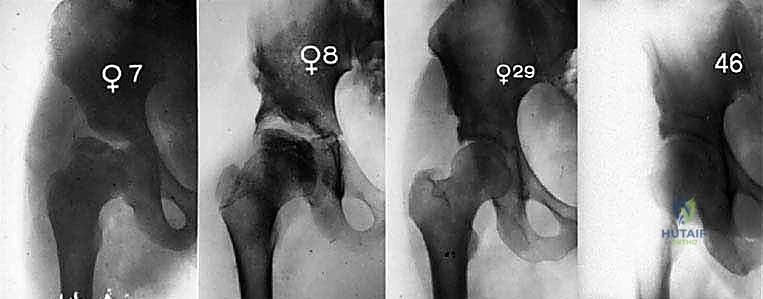

مرض بيرثيز ليس حدثاً مفاجئاً ينتهي بسرعة، بل هو عملية تستمر لسنوات وتمر بأربع مراحل رئيسية. يوضح الجدول التالي هذه المراحل لمساعدة الآباء على فهم تطور الحالة:

| الأولى | مرحلة النخر (Necrosis) | ينقطع الدم عن رأس الفخذ، وتموت الخلايا العظمية. يبدأ المفصل بالالتهاب. | ألم خفيف في الفخذ أو الركبة، عرج بسيط يزداد مع النشاط البدني. |

| الثانية | التفتت (Fragmentation) | يقوم الجسم بإزالة العظم الميت. يصبح رأس الفخذ هشاً جداً ويبدأ في التسطح والتشوه. | زيادة ملحوظة في الألم، قصر في الساق المصابة، تيبس شديد، ومحدودية في الحركة. |

| الثالثة | إعادة التعظم (Reossification) | يبدأ الجسم في بناء عظم جديد لتشكيل رأس الفخذ مرة أخرى. تستمر هذه المرحلة لسنوات. | يقل الألم تدريجياً، لكن شكل رأس الفخذ الجديد يعتمد على مدى الحماية التي تلقاها في المرحلة السابقة. |

| الرابعة | إعادة التشكيل (Remodeling) | يكتمل بناء العظم الجديد. يتخذ رأس الفخذ شكله النهائي (إما كروي سليم أو مشوه). | استقرار الحالة، ولكن إذا كان العظم مشوهاً، سيبدأ الطفل في المعاناة من ألم ميكانيكي مزمن. |

لا تتطلب كل حالات بيرثيز تدخلاً جراحياً. الأطفال الذين يصابون بالمرض في سن مبكرة جداً (أقل من 6 سنوات) غالباً ما يستجيبون للعلاج التحفظي لأن لديهم وقتاً أطول لإعادة تشكيل العظم بشكل طبيعي. ومع ذلك، في الحالات المتقدمة، والأطفال الأكبر سناً، وعند ظهور علامات "الخطر" في الأشعة السينية، يصبح التدخل الجراحي حتمياً.